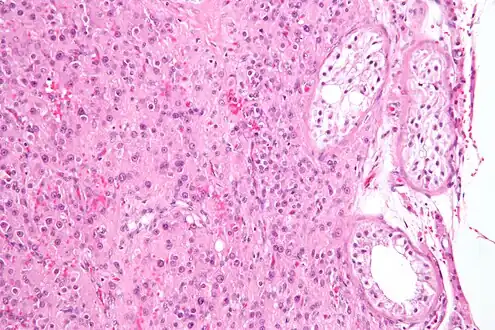

| Histopathology of a Leydig cell tumor, high magnification, H&E stain, showing typical features.[1] | |

A conclusive diagnosis is made via histology, as part of a pathology report made during or after surgery. Reinke crystals are classically found in these tumours and help confirm the diagnosis, although they are seen in less than half of all Leydig cell tumours. Immunohistochemical markers of Leydig cell tumours include inhibin-alpha, calretinin, and melan-A.[6]

High magnification micrograph of a Leydig cell tumour. H&E stain.